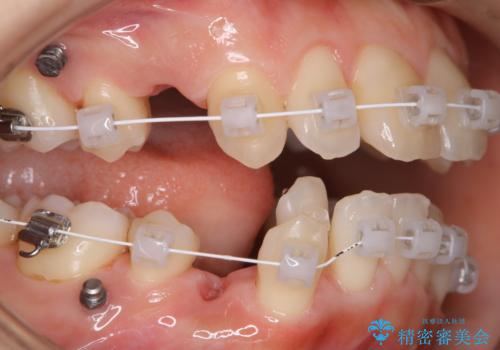

ワイヤー矯正中のクリーニング PMTC

- 審美装置でワイヤー矯正中の患者様です。装置の周りの着色や、抜歯したところのまわりなど全体的な汚れが気になるとのことでPMTC30分コースを行いました。

ワイヤー矯正は歯磨きが難しくなるものです。歯を動かしていることによりできてくるすき間や抜歯矯正の場合は大きなスペースがあります。特にそのような所には汚れがたまりやすくなります。そのため、着色がついたり、虫歯や歯周病、口臭のリスクが高くなります。毎日の歯磨きだけでは100%磨ききることは難しため、ワイヤー調整の診察の際など、定期的にクリーニングすることがおススメです。歯科医院にて、クリーニングを行う場合には、専門的な機械や材料が使用できるため、虫歯・歯周病・口臭などの予防効果も抜群です。